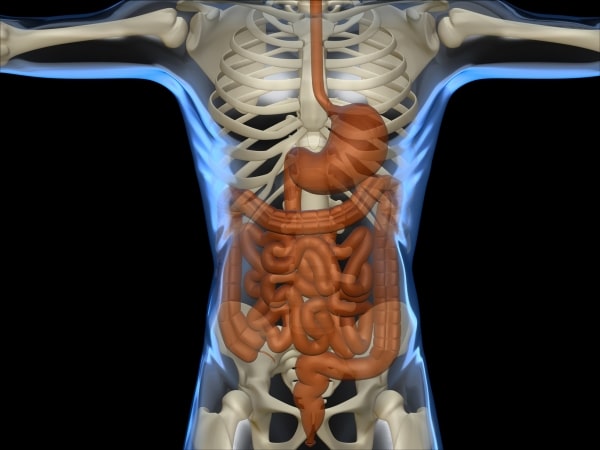

Destination : l’estomac. Pour s’y rendre, il faut passer par l’œsophage. Ce long tube fait progresser la nourriture en se contractant. C’est ce qu’on appelle le péristaltisme. Ce processus est tellement efficace qu’il peut déjouer la gravité : même si l’on mange la tête en bas, les aliments se rendront quand même dans l’estomac. En tout, le voyage dure de quatre à huit secondes pour les aliments solides et à peine deux secondes pour les liquides.

Le séjour dans l’estomac n’est pas très reposant. De l’acide chlorhydrique assez puissant pour dissoudre des clous achève de défigurer ce que tu as avalé. Soupe aux légumes, pâté chinois, tarte aux pommes, les voilà méconnaissables !

Prochaine escale : l’intestin grêle. C’est là que se déroule la majeure partie du travail digestif. La bile déversée par le foie s’occupe des graisses. C’est ce liquide jaunâtre qui est responsable de la coloration brune des selles. Sans bile, les selles seraient d’un blanc grisâtre. Diverses enzymes digestives sécrétées par le pancréas achèvent de décomposer les aliments en particules minuscules. Celles-ci traverseront finalement les parois de l’intestin grêle pour aller « nourrir » chacune des cellules de ton corps en voyageant dans ton sang.

Certains résidus ne sont pas utiles à ton organisme. Ils s’accumulent dans le gros intestin où des millions de bactéries se chargent de les dégrader. Puis, ce qui reste (eau, fibres, mucus, cellules mortes et quelques bactéries) est évacué du gros intestin vers le rectum, puis du rectum à l’anus sous forme d’excréments.